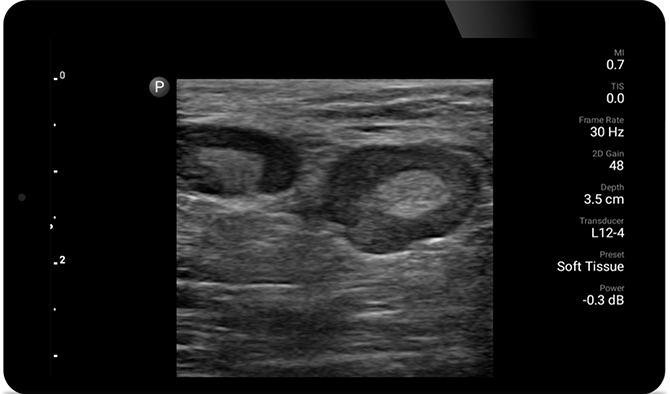

POC ultrasound for soft tissue

Ultrasound exams can improve your ability to identify and successfully treat skin abscesses.